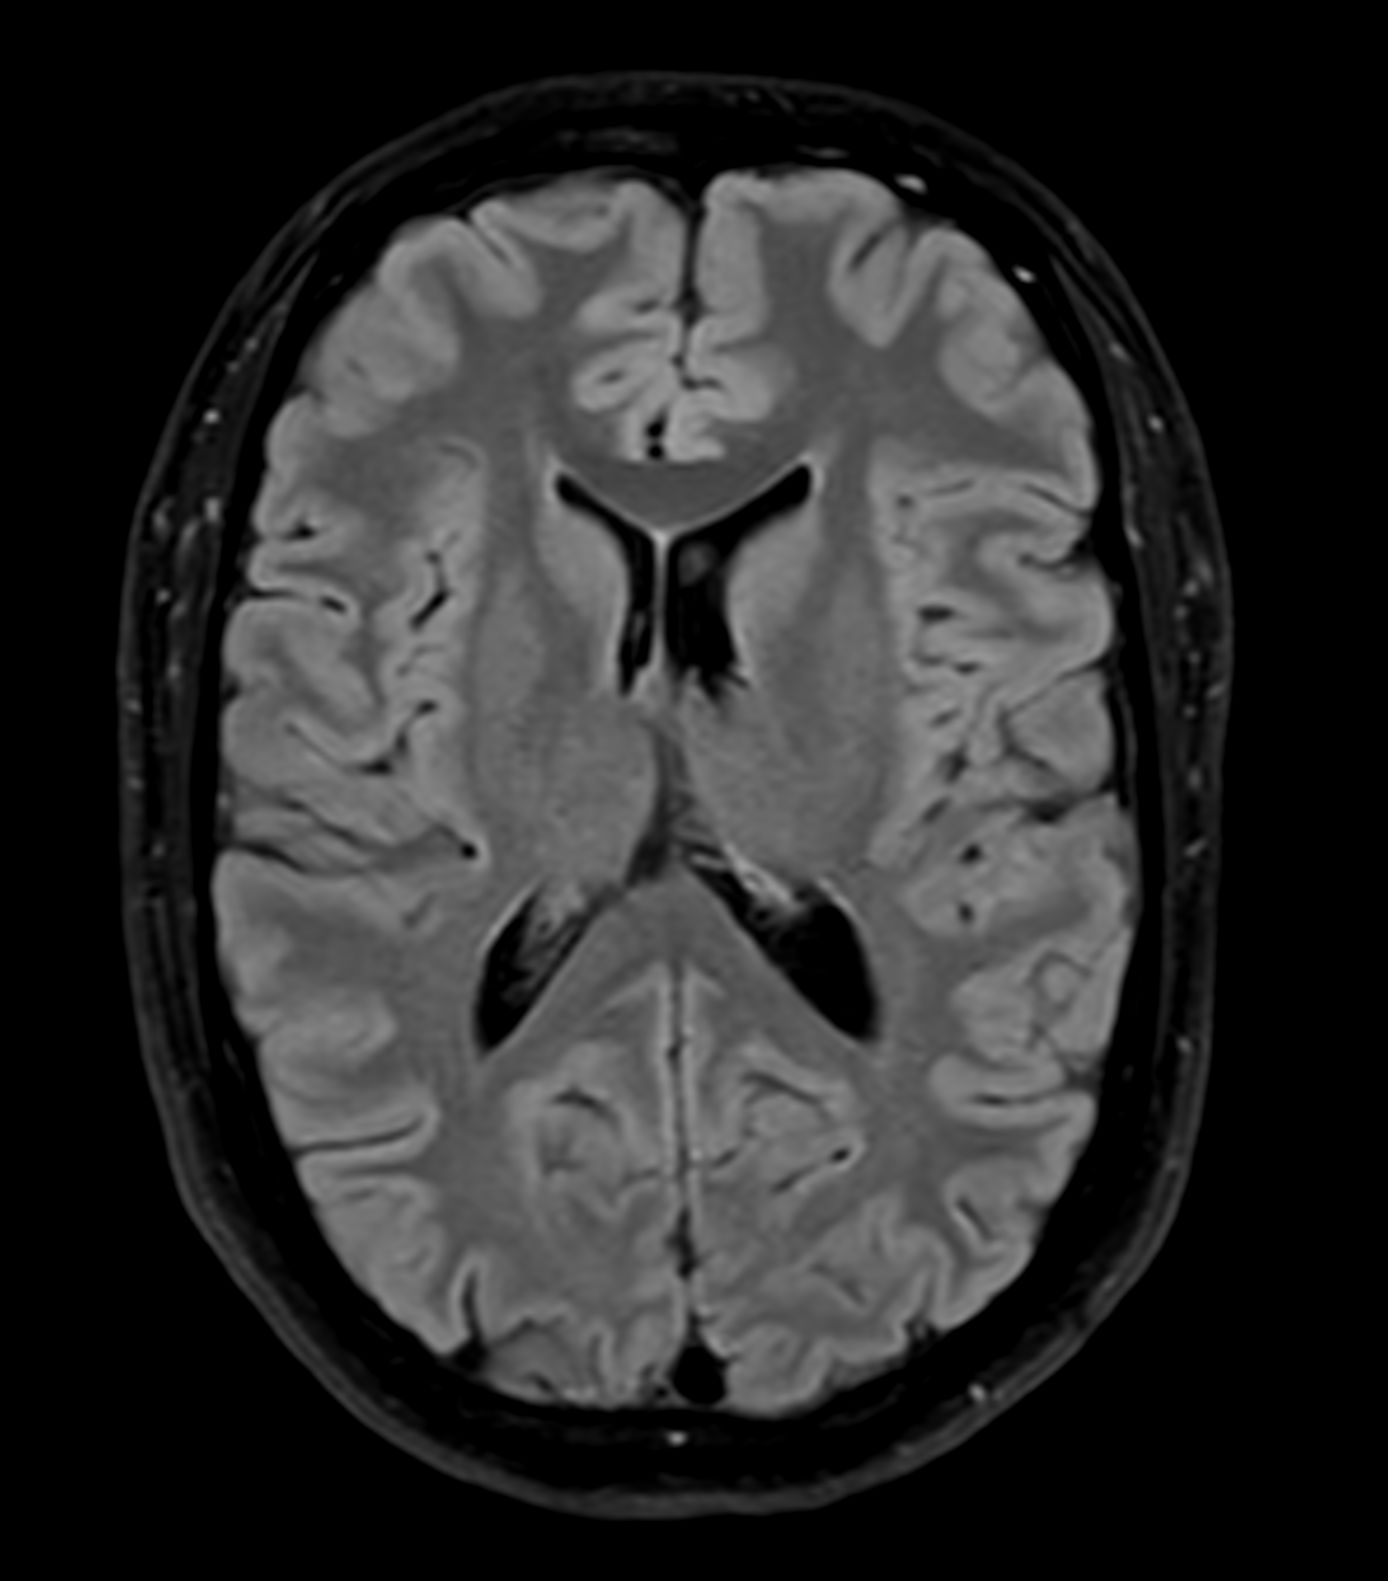

Alzheimer’s Disease Anti-Amyloid Immunotherapies (ARIA) 1.5T

Amyloid clearing medication, such as Aduhelm (Aducanumab) and Leqembi (Lecanemab) have been cleared by the FDA in 2022/2023, to slow down cognitive decline in early-stage Alzheimer’s disease. ASNR-recommendations for AD therapeutic imaging were published in 2022 for eligibility assessment as well as for monitoring for amyloid-related imaging abnormalities. This ExamCard includes ASNR-recommended consensus protocols for imaging of Alzheimer’s Disease Anti-Amyloid Immunotherapies (ARIA). (Cogswell et al., AJNR 2022,43(9)E19-E35;DOI: https://doi.org/10.3174/ajnr.A7586))